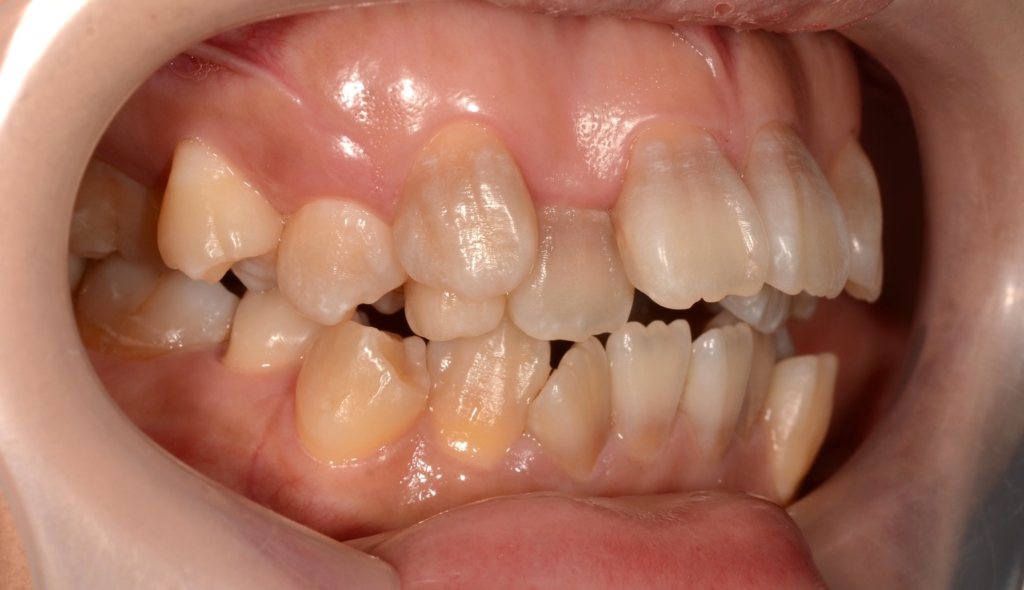

【Before】

#1.顎と歯の不調和による叢生(重度)

#2.上顎前突(出っ歯)

#3.開口

と診断しました。